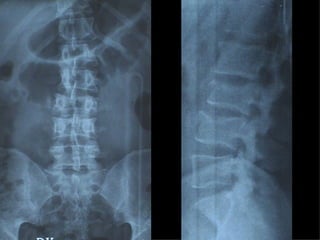

Fratture della colonna vetebrale

Tc pre op